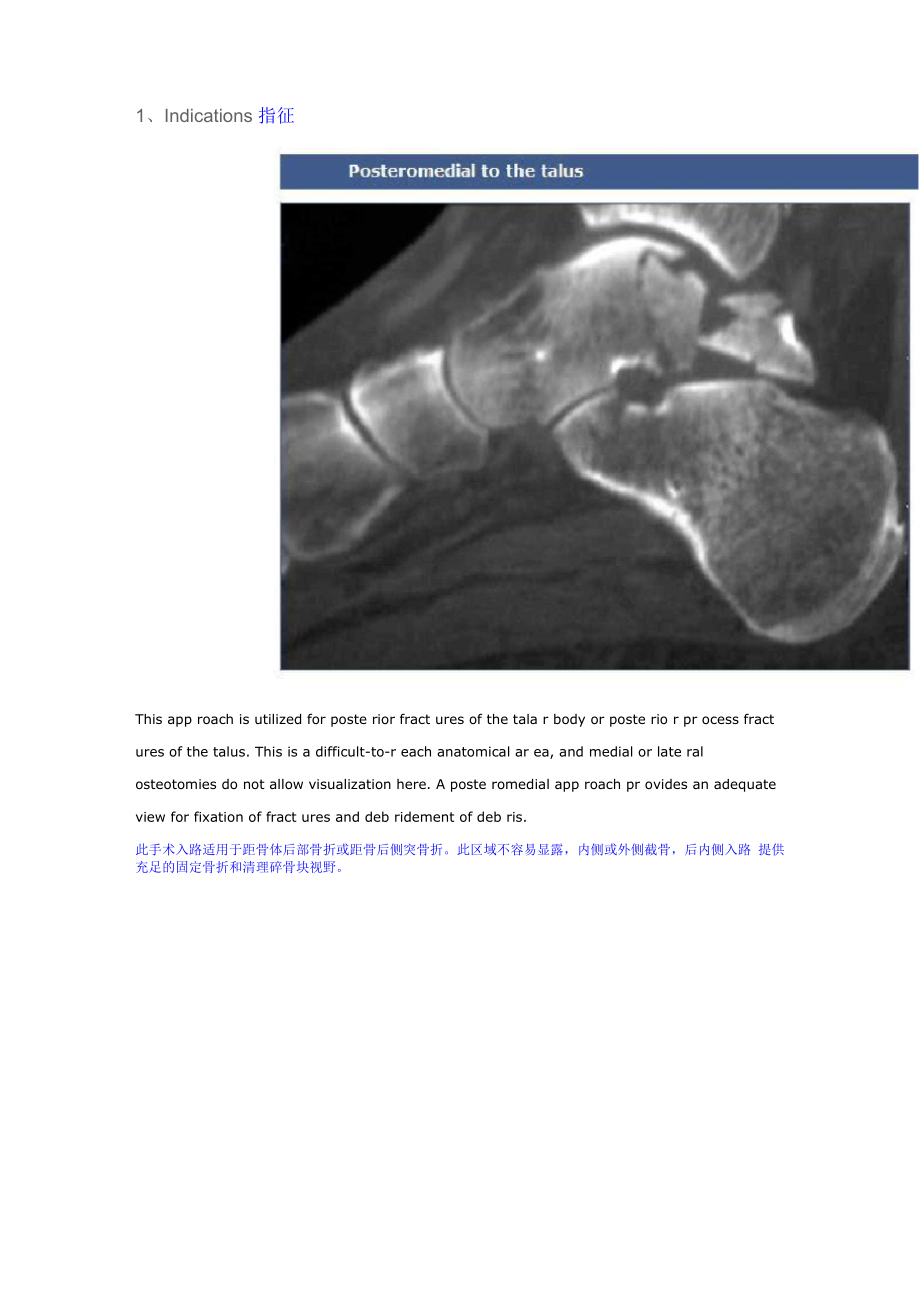

1、Indications 指征This app roach is utilized for poste rior fract ures of the tala r body or poste rio r pr ocess fract ures of the talus. This is a difficult-to-r each anatomical ar ea, and medial or late ral osteotomies do not allow visualization here. A poste romedial app roach pr ovides an adequate view for fixation of fract ures and deb ridement of deb ris.此手术入路适用于距骨体后部骨折或距骨后侧突骨折此区域不容易显露,内侧或外侧截骨,后内侧入路 提供充足的固定骨折和清理碎骨块视野The poste romedial app roach is used rar ely and would expose a fract ure of the poste rior pr ocess of the talus, but would not give visualization of the tala r body, or the subtala r joint. Fr act ures of the body of the talus most often r equi re, par ticula rly if they are more poste rior, an osteotomy of the medial malleolus.后内侧入路通常很少使用,可以显露距骨后突骨折块,但是却无法看见距骨体, 距下关节。